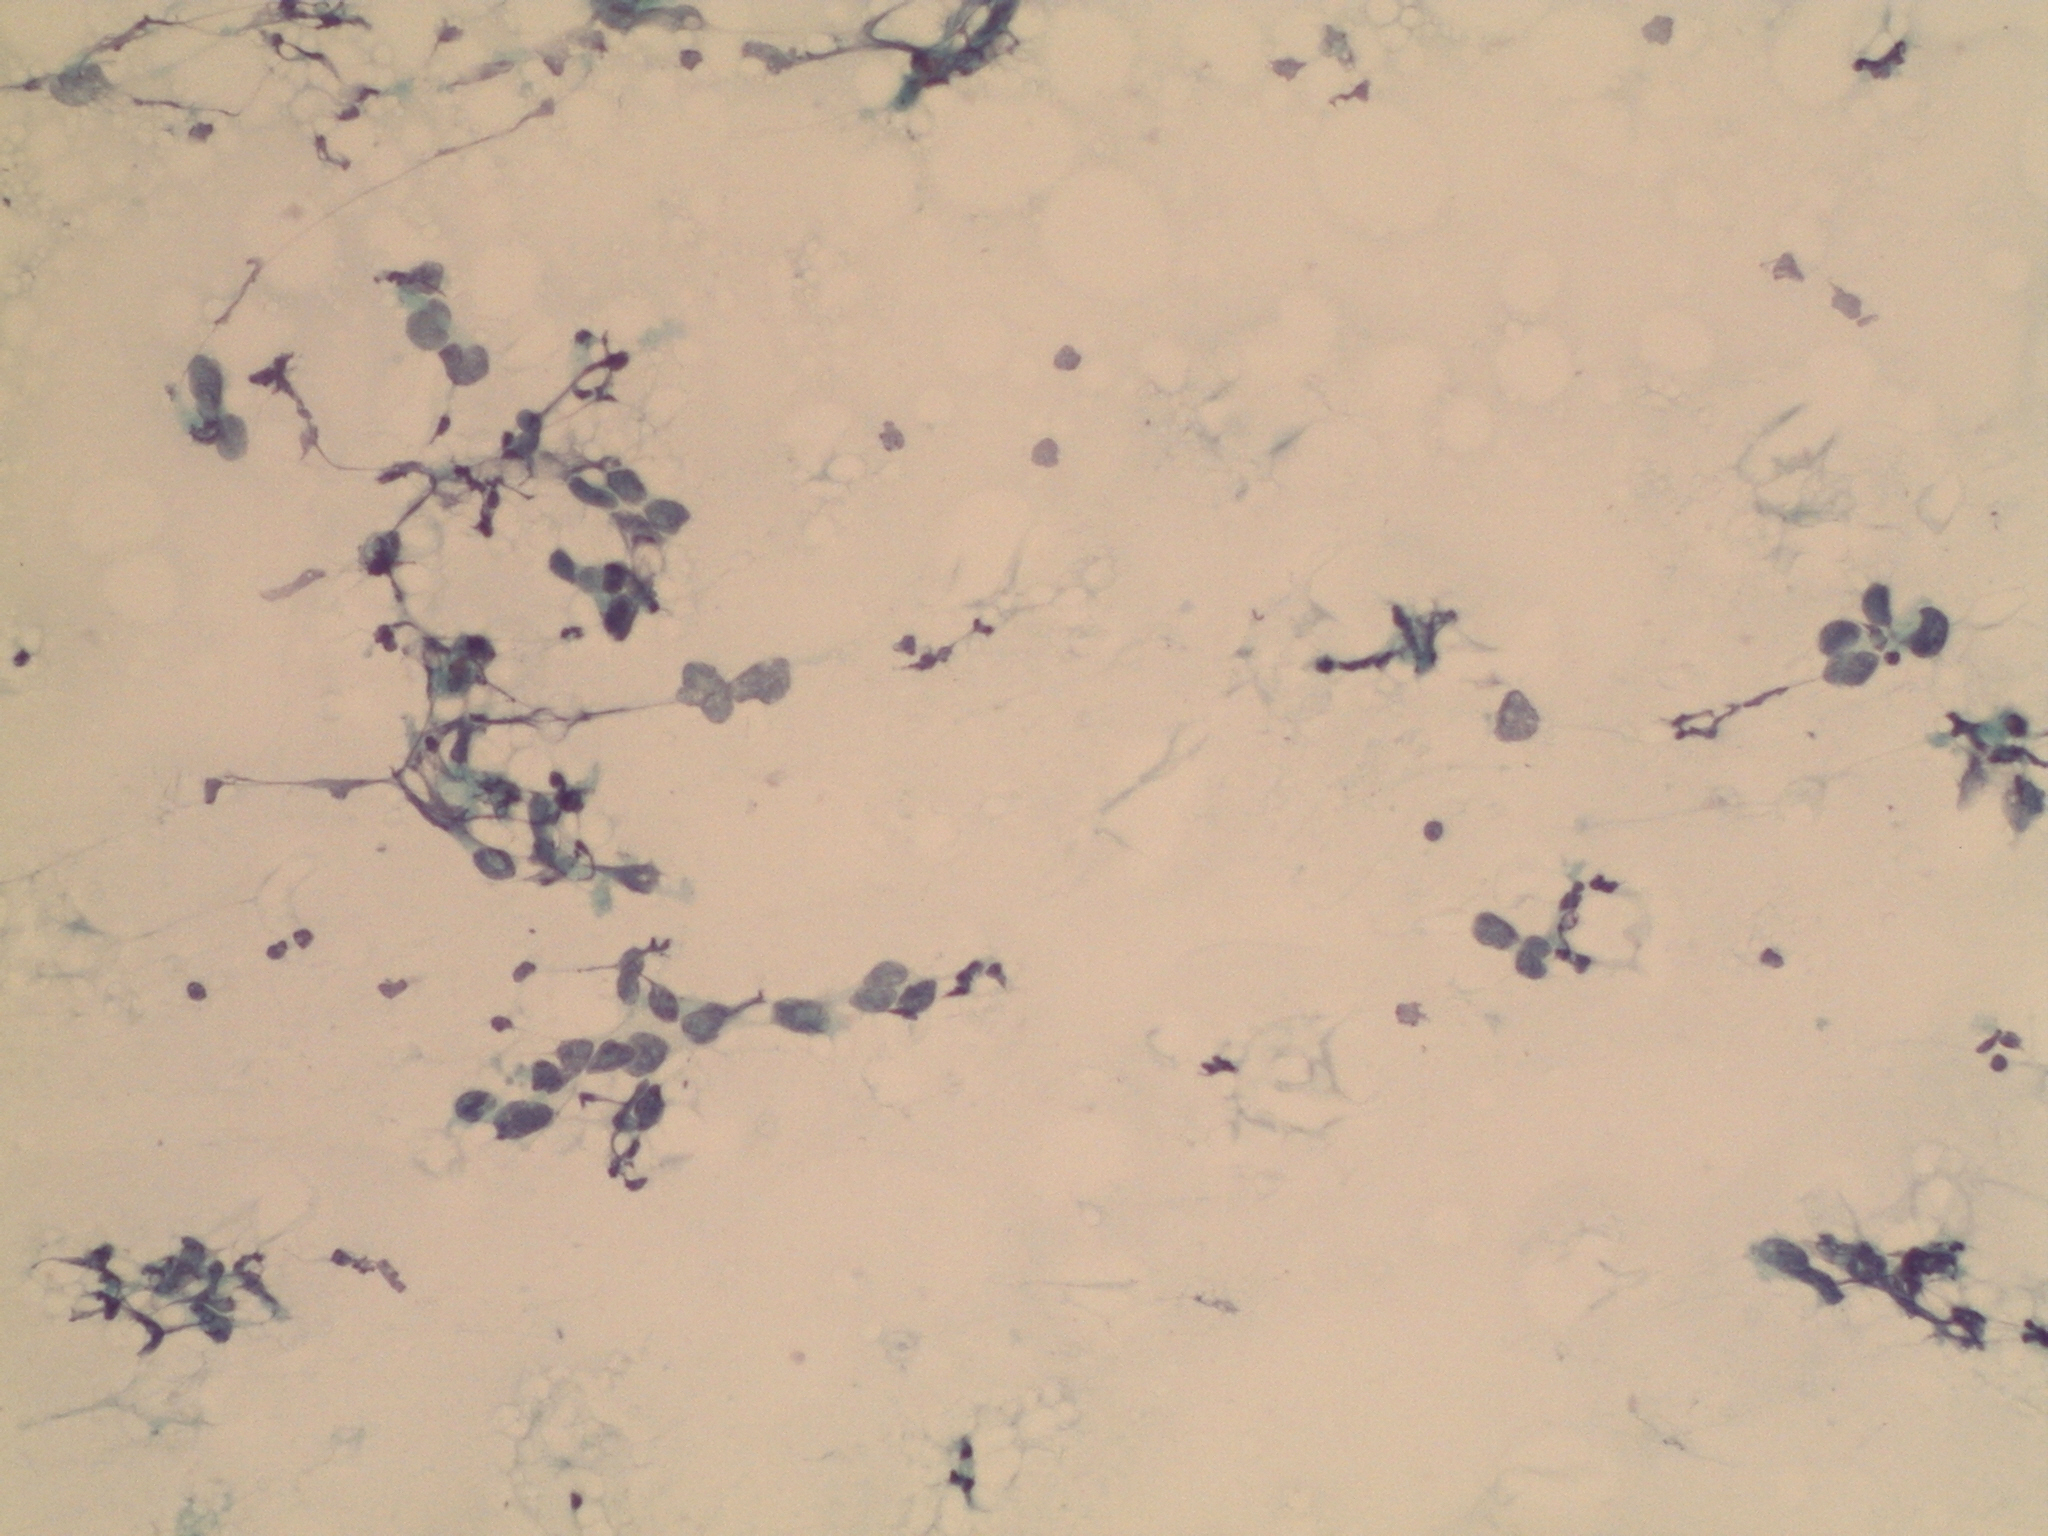

Dona de 59 anys, fumadora de 15-20 cigarretes/dia fins fa 10 anys, sense altres hàbits tòxics destacables, amb antecedents patològics de Diabetes Mellitus tipus I que tracta amb insulina, Hipertensió arterial, i dislipèmia. Consulta per cuadre progressiu desde fa 5-6 mesos d'anosmia, cefalees hemicraneals esquerres, hipoestesia d'hemicara esquerra, epistaxis esquerres que es fan diàries, visió borrosa amb diplòpia, i tumefacció cervical esquerra. A l'exploració física s'observa exoftalmos esquerre i adenopaties laterocervicals esquerres indurades, i a l'estudi ORL s'observa lesió polipoidea eritematosa a fossa nasal provinent de meat superior esquerre. Es realitzen diverses proves de Diagnòstic per la imatge, i es realitzen simultàniament punció aspirativa i biòpsia de la lesió a fossa nasal. S'adjunten imatges de la RNM cranial, i de punció aspirativa.